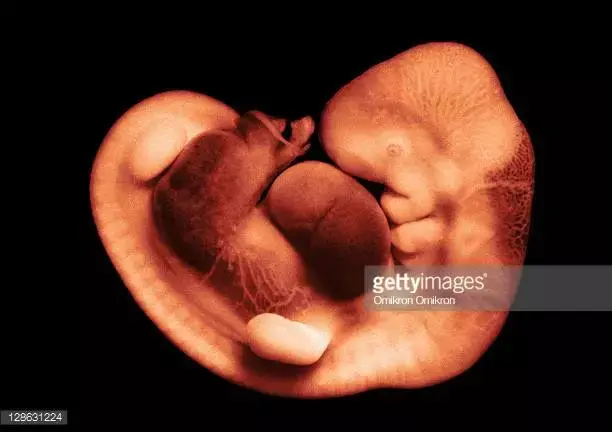

因為胚胎的發育,孕30—40天形成胎囊,孕40—50天形成胎芽,孕50—60天形成胎心。40天左右做B超檢查,是能夠看到胎芽有0.5-1厘米大小,形狀如小海馬的。如果沒有發現胎芽,孕媽媽就要引起重視。

胎兒長到0.4厘米,進入了胚胎期,羊膜腔擴大,原始心血管出現,可有搏動。B超可看見小胎囊,胎囊約占宮腔不到1/4,或可見胎芽。它蘋果籽一樣大小,外觀像個“小海馬”。